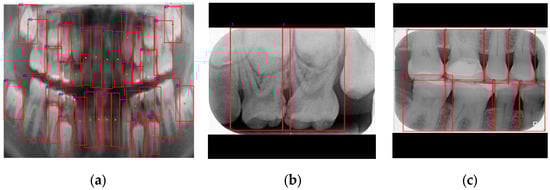

| Cutting Black Borders + Padding | Sharpening + Median Filtering | |

|---|---|---|

| Precision ↑ | 95.07 | 98.16 |

| Recall ↑ | 97.86 | 98.44 |

| mAP50 ↑ | 98.22 | 98.48 |

| mAP50~95 ↑ | 70.18 | 72.94 |

| F1-score ↑ | 96.44 | 98.30 |

| Image | ![]() | ![]() |